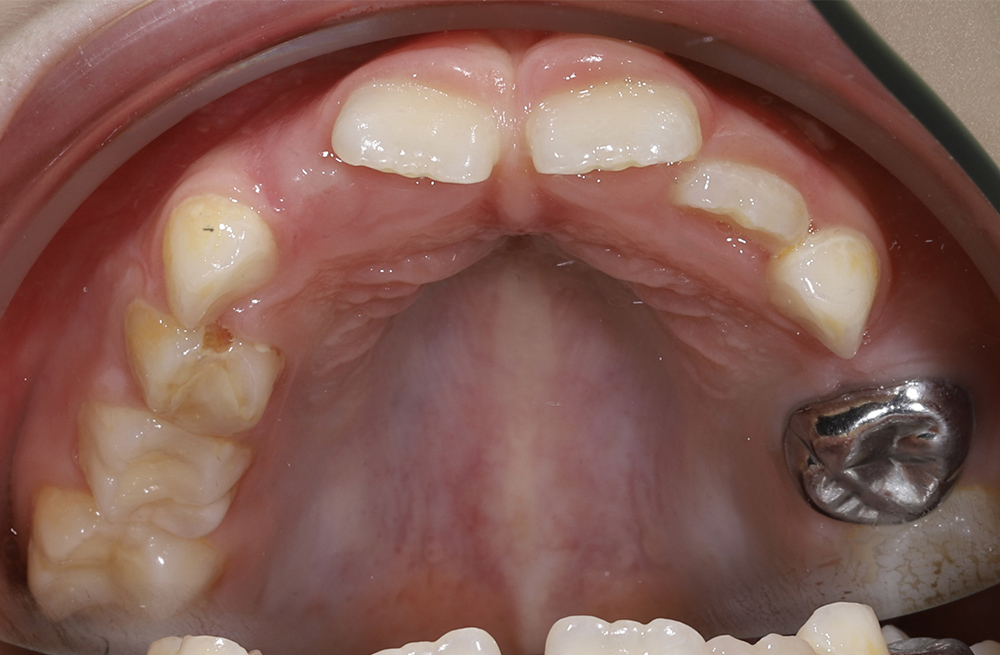

Комплексное ортодонтическое лечение у девушки с множественными нарушениями прикуса на фоне врождённой адентии боковых резцов